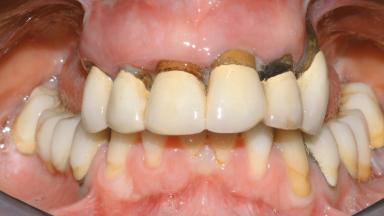

A 35-year-old Caucasian female presenting with advanced periodontal disease involving both the maxillary and the mandibular dentition was referred for evaluation. The patient, a non-smoker in good general health, requested treatment for recurrent periodontal abscesses, tooth mobility, and discomfort during chewing, as well as restoration of her missing teeth with a fixed prosthesis to improve mastication and esthetics. All residual maxillary teeth exhibited plaque deposits, deep pockets, bleeding on probing, and class III mobility and were evaluated as hopeless. All residual mandibular teeth except tooth 37 could be maintained after periodontal therapy.

Defining Characteristics Fully edentulous upper jaw to be rehabilitated with an implant-borne fixed dental prosthesis